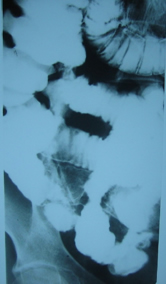

Στους ίδιους ασθενείς η εντερόκλυση μπορεί να αναδείξει ανάλογα ευρήματα με την ενδοσκοπική κάψουλα (εικόνες 36-43) ή να είναι φυσιολογική (εικόνες 44-48).

38  39

Εικόνα 38. Ο ίδιος ασθενής με τις εικόνες 10,13.          Εικόνα 39. Ο ίδιος ασθενής με τις εικόνες 33,34.

Στένωση τελικού ειλεού                                                  Εξελκώσεις τελικού ειλεού